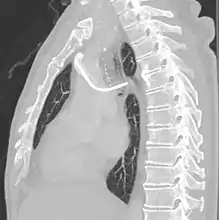

Azygos vein